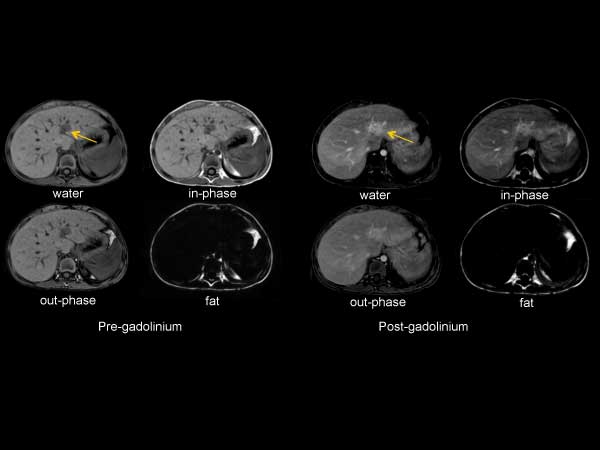

Axial mDIXON (Free Breath)